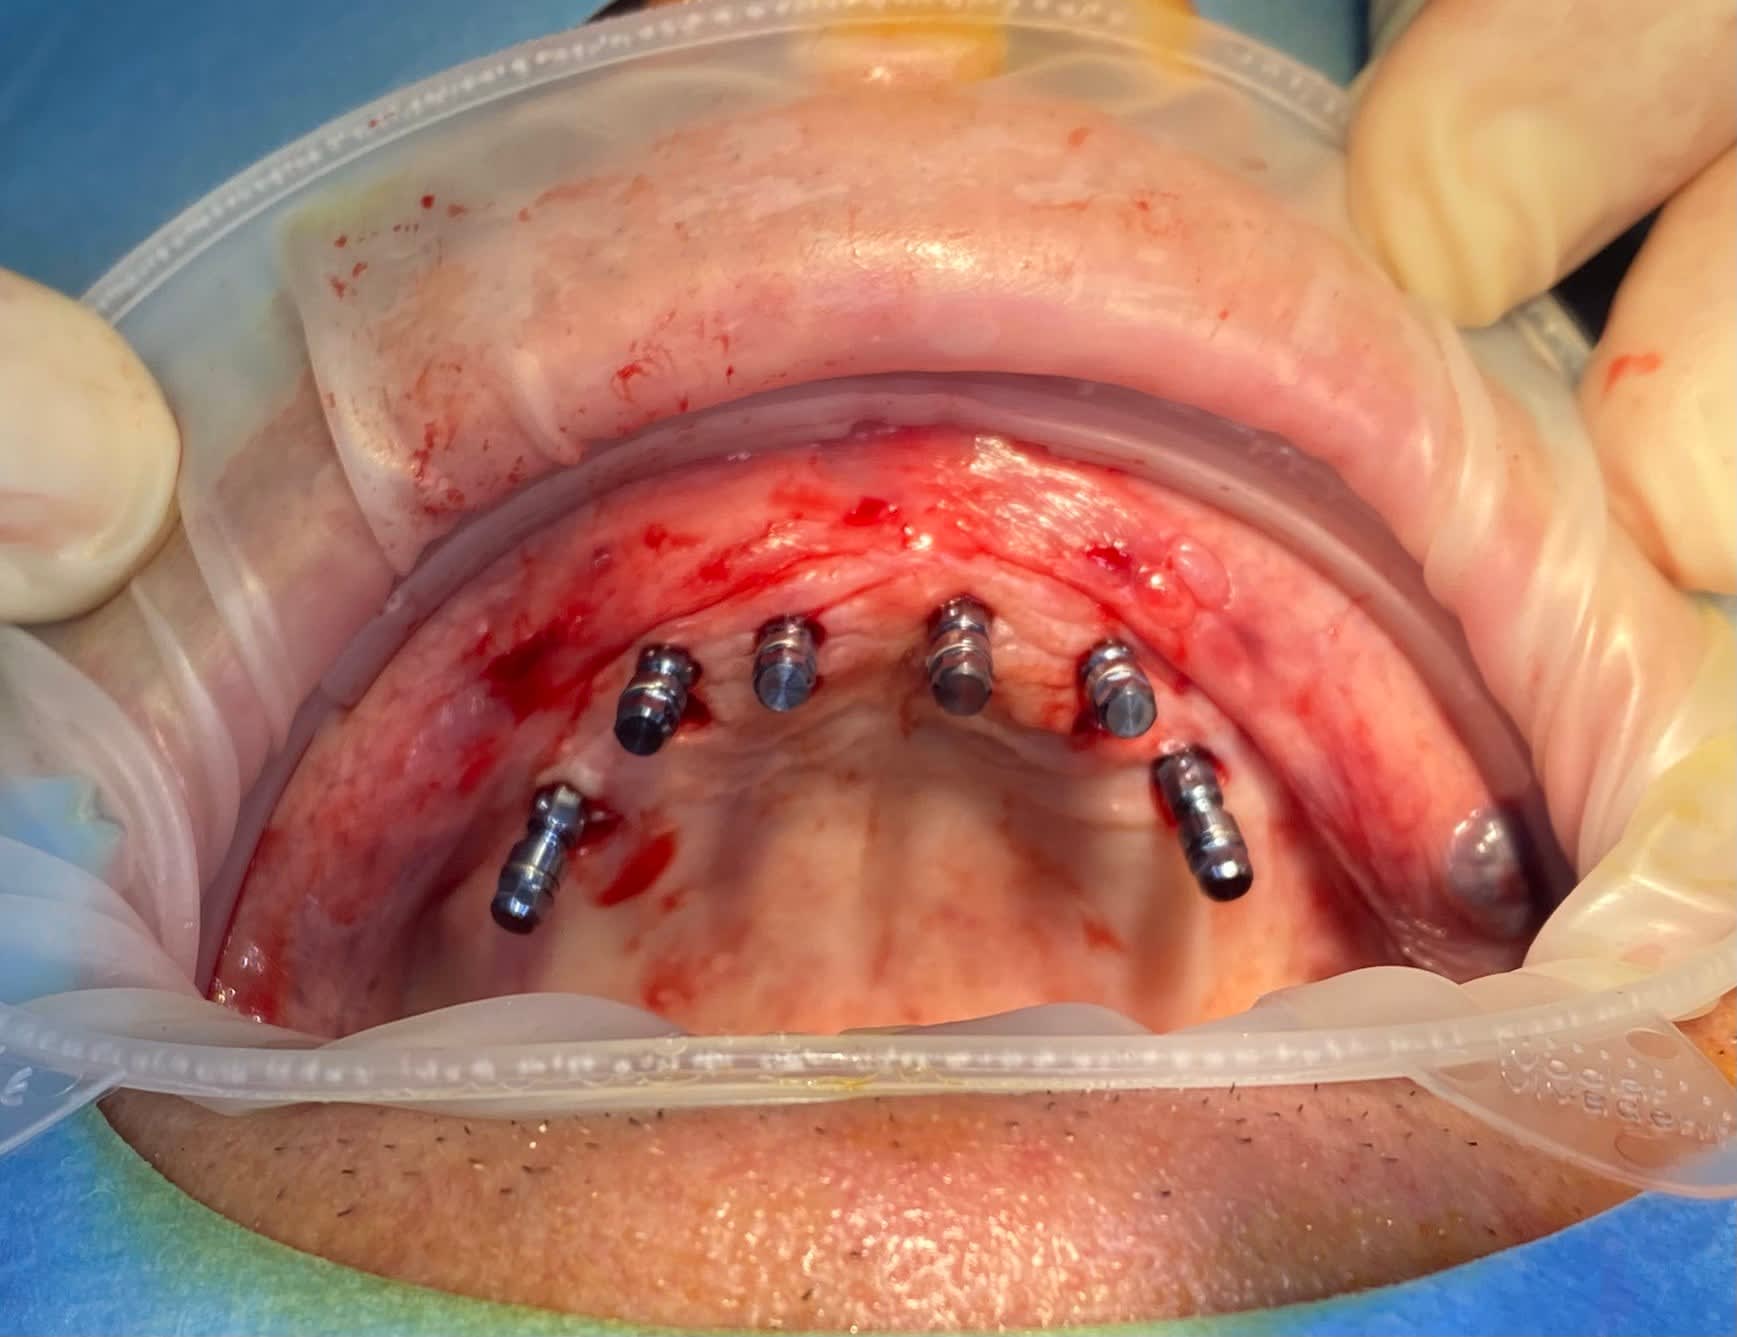

Patient de 80 ans, bon état de santé générale, édenté complet depuis une vingtaine d'année. Il décide qu'il en a marre que ses prothèses bougent quand il parle, surtout la mandibulaire, donc 2019 on met 4 mini-implants pour stabiliser la prothèse du bas. Le patient a peu de moyens financiers et ne souhaite pas de réhabilitation fixe.

2022, il trouve que c'est très sympa que la prothèse soit fixée, il me demande donc de faire la même chose en haut, et il souhaite passer à la prothèse fixée maxillaire mais en 2023 le temps de retrouver des finances...

Pose de 6 implants Straumann SLactive maxillaires, avec guide chirurgical complet full-guided en flapless. La prothèse amovible actuelle du patient sera stabilisée sur 6 Novaloc dans 6 semaines le temps que le patient donne le feu vert pour la prothèse fixée.

Petit cas simple, mais c'était mon premier cas de complet, toutes les critiques sont les bienvenues